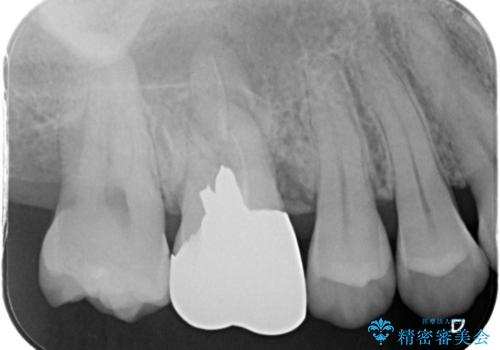

- 右上4、5の歯がしみるのを治したいという主訴で来院されました。精査の結果隣接面う蝕と診断し、適合がよく見ためも良いセラミックインレーでの治療を行いました。

セラミックインレーを入れた後は歯がしみることはなくなり、白く丈夫な被せ物が入り満足いただけました。